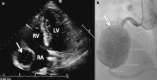

Cardiac vasculitis is recognized as a heterogeneous disease process with a wide spectrum of manifestations including pericarditis, myocarditis, valvular heart disease and less frequently, coronary artery vasculitis (CAV). CAV encompasses an emerging field of diseases which differ from conventional atherosclerotic disease and have a proclivity for the younger population groups. CAV portends multiple complications including the development of coronary artery aneurysms, coronary stenotic lesions, and thrombosis, all which may result in acute coronary syndromes. There are several aetiologies for CAV; with Kawasaki's disease, Takayasu's arteritis, Polyarteritis Nodosa, and Giant-Cell Arteritis more frequently described clinically, and in literature. There is a growing role for multi-modality imaging in assisting the diagnostic process; including transthoracic echocardiography, cardiac magnetic resonance imaging, computed tomography coronary angiography, fluorodeoxyglucose-positron emission tomography and conventional coronary angiogram with intravascular ultrasound. Whilst the treatment paradigms fundamentally vary between different aetiologies, there are overlaps with pharmacological regimes in immunosuppressive agents and anti-platelet therapies. Interventional and surgical management are is a consideration in select populations groups, within a multi-disciplinary context. Further large-scale studies are required to better appropriately outline management protocols in this niche population.